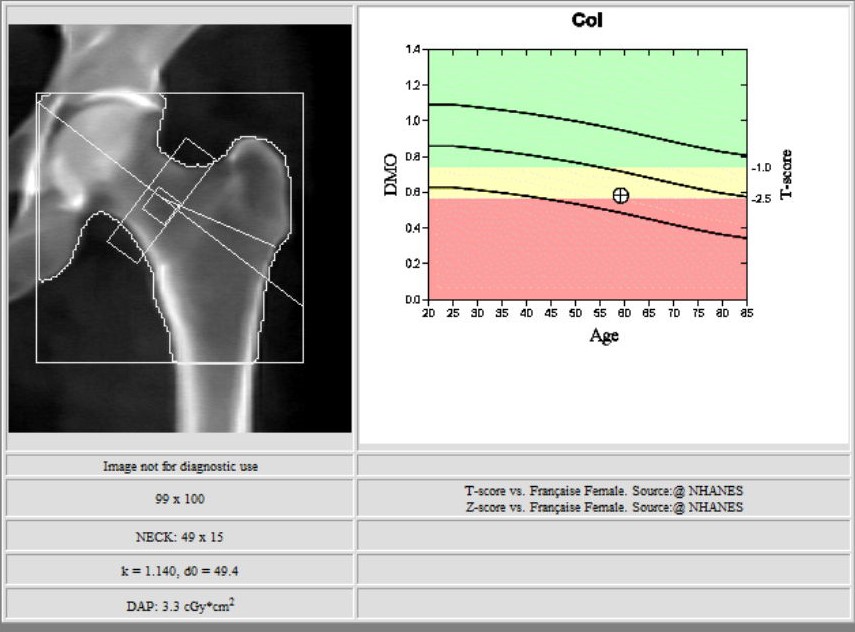

L’ostéodensitométrie mesure précisément la densité osseuse au niveau de deux sites principaux (souvent le rachis lombaire et le col fémoral), grâce à une technique dite biphotonique utilisant deux faisceaux de rayons X à très faible dose.

Elle constitue aujourd’hui la méthode la plus précise et la plus fiable pour diagnostiquer l’ostéoporose et évaluer le risque de fracture.

2. la hanche.